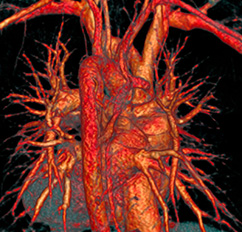

Zu den häufigsten Herzerkrankungen zählt in Deutschland die sogenannte koronare Herzkrankheit (KHK). Dabei handelt es sich um Verengungen (Stenosen) der Herzkranzgefäße, welche durch Wandveränderungen (Arteriosklerose) der Herzkranzgefäße bedingt sind. Diese Verengungen können zu Durchblutungsstörungen des Herzmuskels führen. Je nachdem wie hochgradig diese Verengungen sind, können sie einen Herzinfarkt oder die typischen Beschwerden einer Angina pectoris (z. B. Engegefühl in der Brust) auslösen. Auch bevor diese typischen Beschwerden eintreten, kann die Durchblutung des Herzens, vor allem unter körperlicher Anstrengung, bereits reduziert sein. Mit der MRT kann festgestellt werden, ob Verengungen der Herzkranzarterien, die zum Beispiel bei einer Computertomographie dieser Gefäße aufgefallen sind, funktionell für die Durchblutung des Herzmuskels relevant und also invasiv therapiewürdig sind. Zusätzlich können nur mit der MRT Narben, zum Beispiel in Folge eines Herzinfarktes ( - der manchmal auch stumm ohne Beschwerden abgelaufen sein kann - ) nachgewiesen und ausgeschlossen werden.

Eine Belastungsuntersuchung zur Messung der Durchblutung des Herzens („Stress-Perfusions-MRT“) hat das Ziel, eine koronare Herzerkrankung festzustellen. Hierfür wird die Herzdurchblutung mittels Kontrastmittel in Ruhe und unter medikamentöser „Belastung“ dargestellt. Dabei wird das Medikament Regadenoson in die Vene gespritzt, das die gesunden Herzkranzarterien maximal erweitert, krankhaft verengte Gefäßanteile aber nicht. Spritzt man dann nach diesem Medikament das MR-Kontrastmittel in die Vene, flutet dieses in den Herzmuskelanteilen, die von einem verengten Herzkranzgefäß vesorgt wereden, sichtbar langsamer und später an als in den Muskelanteilen, die von gesunden Herzkranzgefäßen versorgt sind. Das Medikament Regadenoson verursacht oft ein unangenehmes Druckgefühl im Brustkorb. Es gibt wenige Kontraindikationen gegen dieses Medikament, die wir im Vorfeld über unseren Aufklärungsbogen, den Sie auch schon im Vorfeld über diese Homepage zu Ihrer Information herunterladen können, abfragen. Das Medikament wirkt nicht, wenn Sie am gleichen Tag Kaffee oder schwarzen Tee getrunken haben.